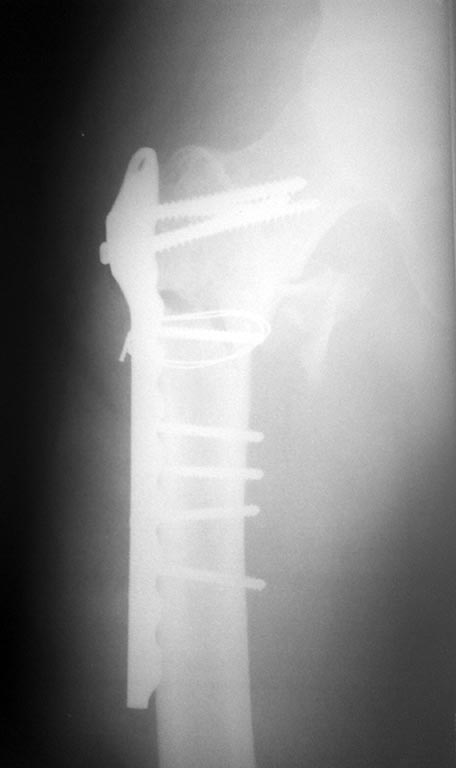

Хотелось бы посмотреть на свежий снимок оперированного отдела бедра. Может, там все развалилось уже, и это и есть причина лихорадки?

после

В сожалению остеосинтез у Вас получился нестабильным, это, опосредованно, может стать причиной лихорадки. Полностью согласен с постом про УЗИ и ревизию. Хочу добавить, что в случае отсутствия гнойного процесса, можно провести в проксимальный отломок более длинные винты.